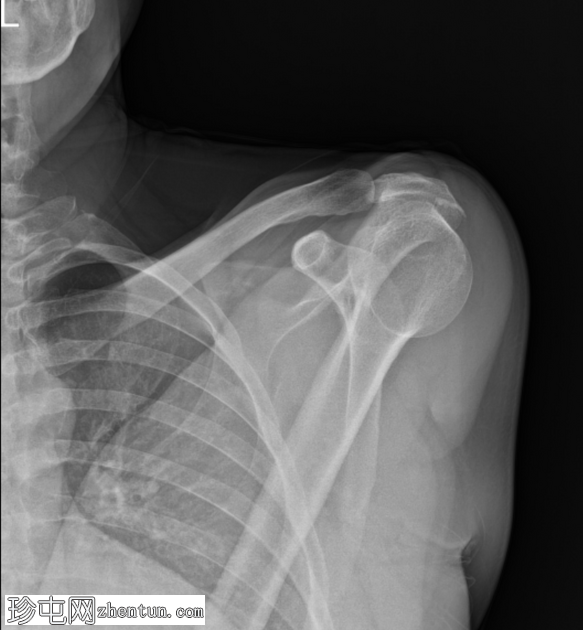

X线片

2.png

斜位

冈上肌腱止点处可见弧形钙化,符合钙化性肌腱炎的影像学表现

未见相关骨骼异常